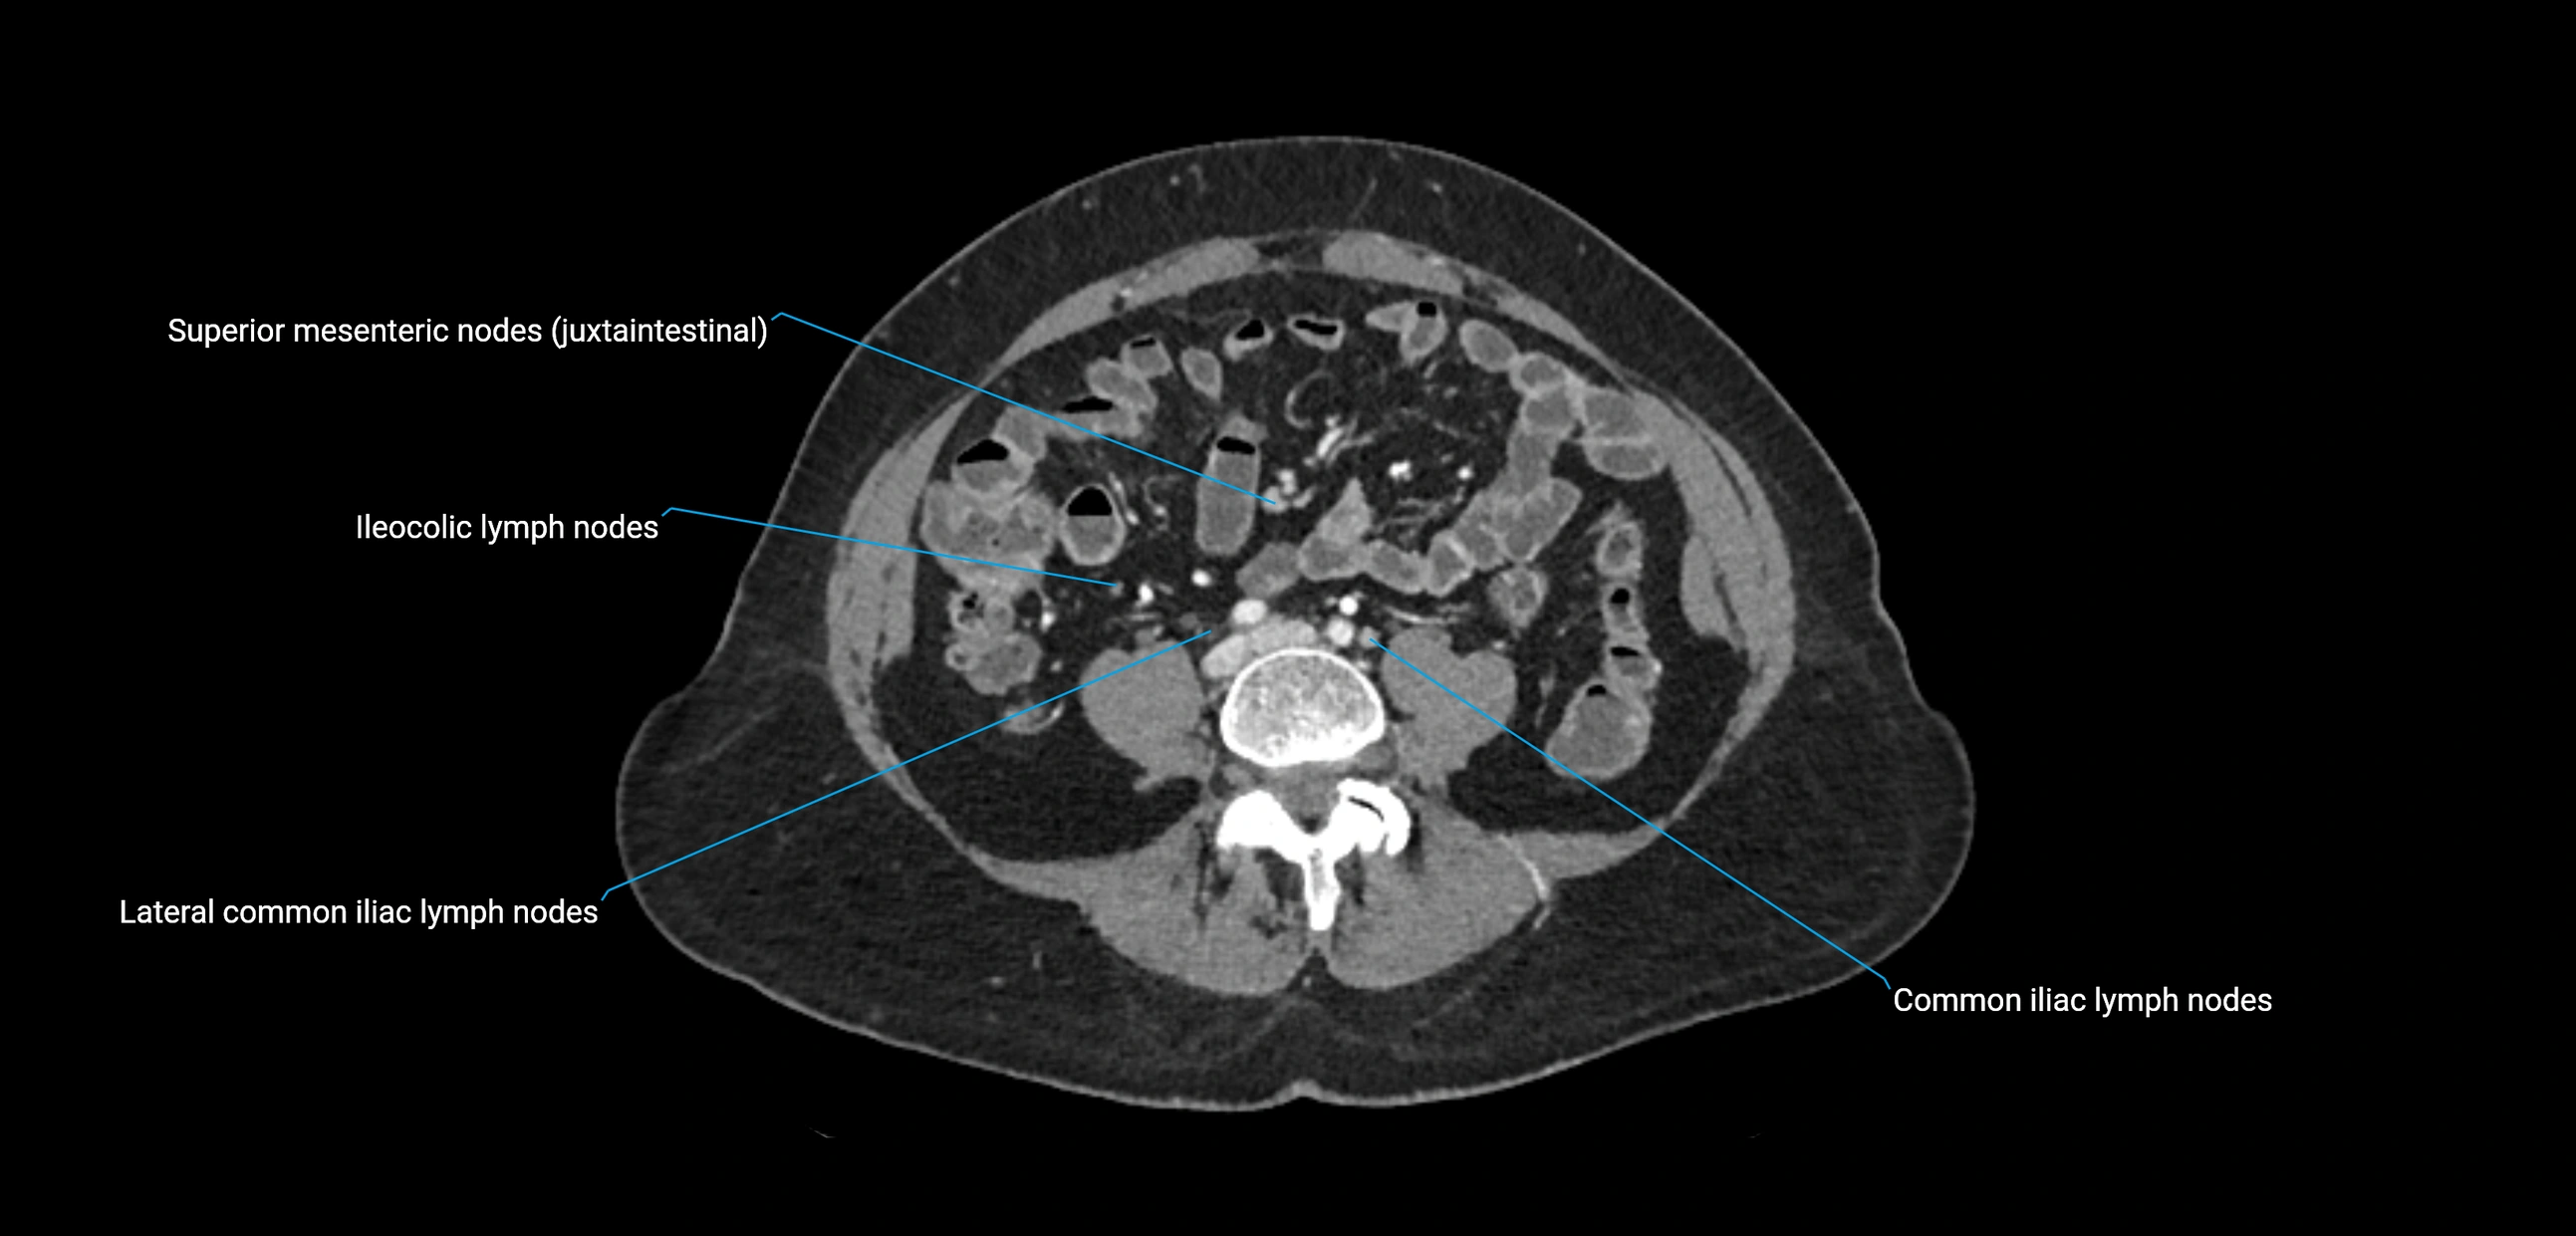

CT image

image